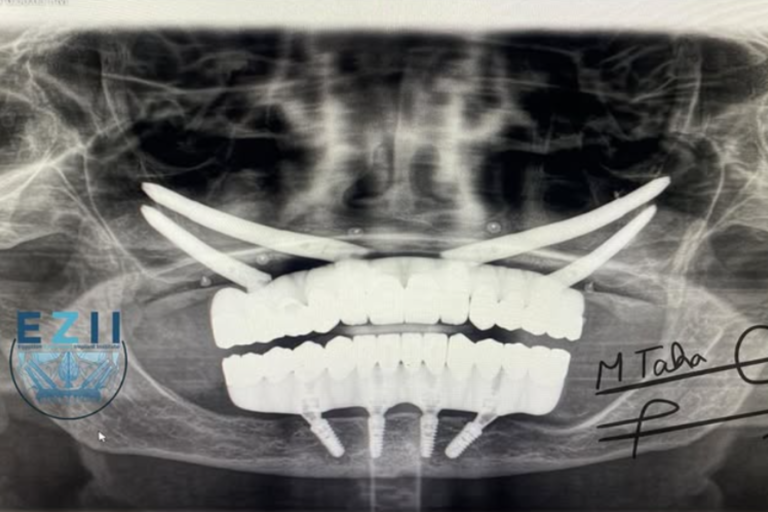

الإجراء الجراحي: استعادة الثبات باستخدام غرسات Zygomatic و All-on-4

تحت التخدير العام، بدأت المرحلة الجراحية. تم وضع أربع غرسات وجنية بشكل استراتيجي في الفك العلوي الضامر بشدة، مما يضمن أساساً ثابتاً لبدلة الأسنان الاصطناعية الجديدة الطرف الاصطناعي الثابت الجديد. بالإضافة إلى ذلك، تم وضع طرف اصطناعي مدعوم بالغرسات من نوع All-on-4 في فكها السفلي، مما يوفر ترميمًا كامل القوس.

بعد فترة الشفاء الأولية، سافرت مريضة الدكتور طه إلى بلدها الأم، وعادت في وقت لاحق لتركيب الطرف الاصطناعي النهائي. تألف الحل النهائي من إطار مخصص من التيتانيوم مع تيجان من الزركونيا – تم اختيارهالمتانتها الاستثنائية وجمالياتها الطبيعية.